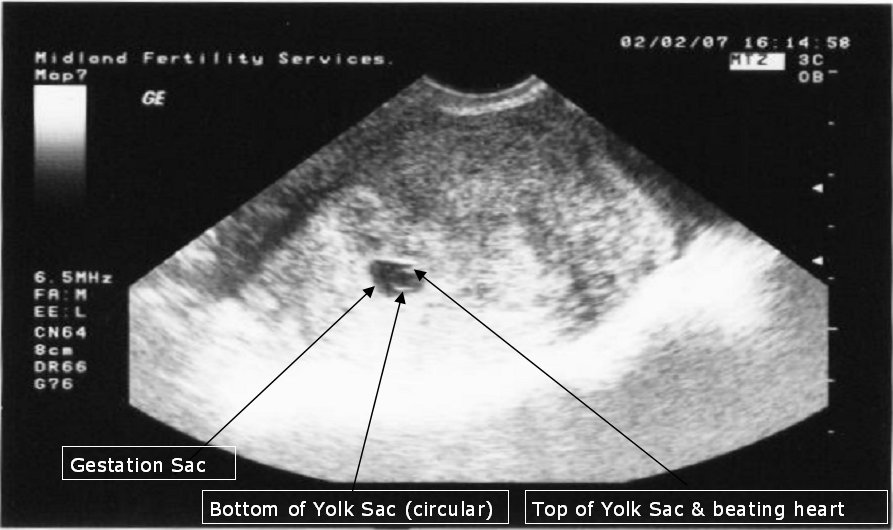

The Midlands Fertility Clinic sign us off and chalk up a successful ICSI IVF treatment for their stats! Juliet's six week scan (actually it's four week since implantation but that's how they calculate it!) showed a strawberry sized gestation sac containing a circular yolk sac and inside that is a grain sized baby with a rapidly beating heart! They give us a 95% chance of a successful live birth now...